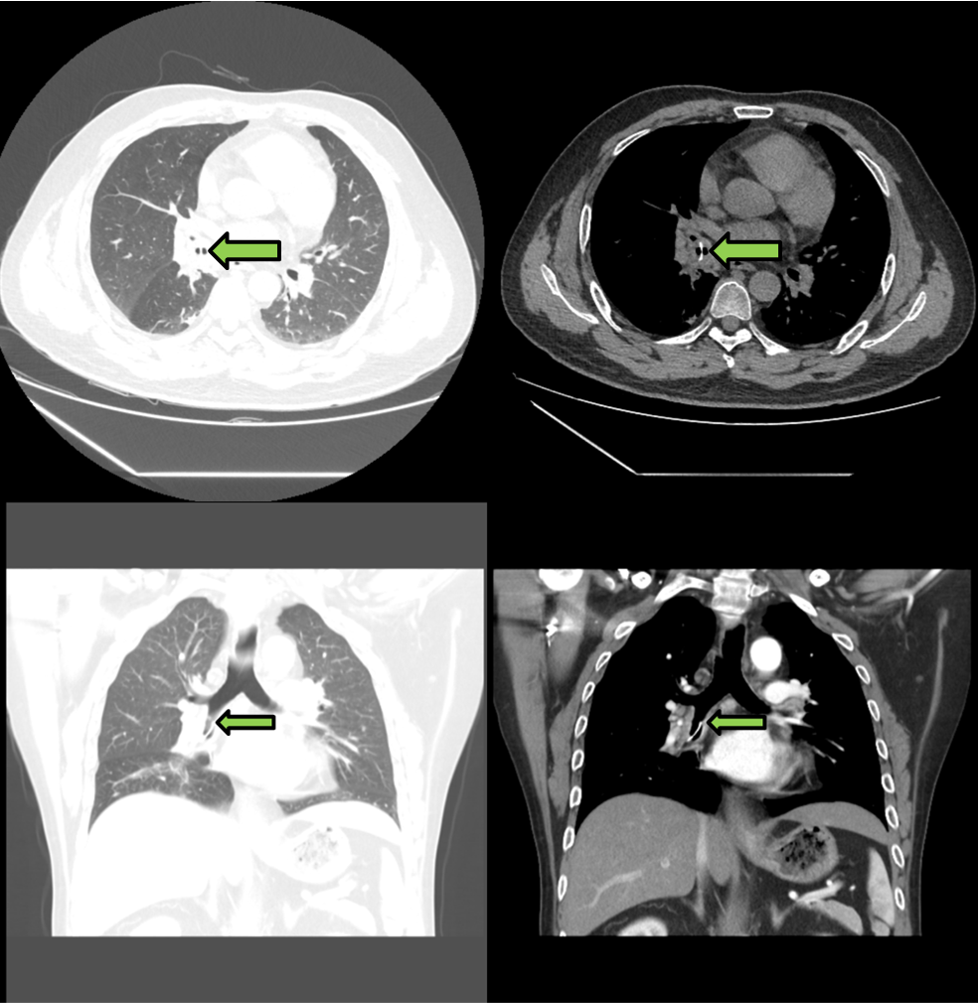

今年3月,一名46岁男性患者前来我院就诊,患者表示前后有四年时间反复出现呼吸困难的情况,尤其近半年愈发严重,呼吸的时候会出现异响,因此来我院就医。呼吸与危重症医学科立即安排患者住院,并且查看到这名患者4年前就在我院确诊慢性阻塞性肺疾病,因为患者有精神类疾病,因此没有进行过规律的治疗。为了进一步完善检查,我院给患者安排了胸部增强CT,提示右肺中叶支气管异物存留并管壁炎性增厚,建议纤支镜检查,同时右肺下叶部分支气管粘液存留,右肺下叶及左肺散在炎症。完善支气管镜后发现中间段支气管内可见一长条形、不规则异物,周围可见大量肉芽组织,管腔轻度狭窄,粘膜表面可见大量白斑及黄白色痰液粘附,下叶支气管开口重度狭窄。

胸部增强CT见异物,伴开口狭窄